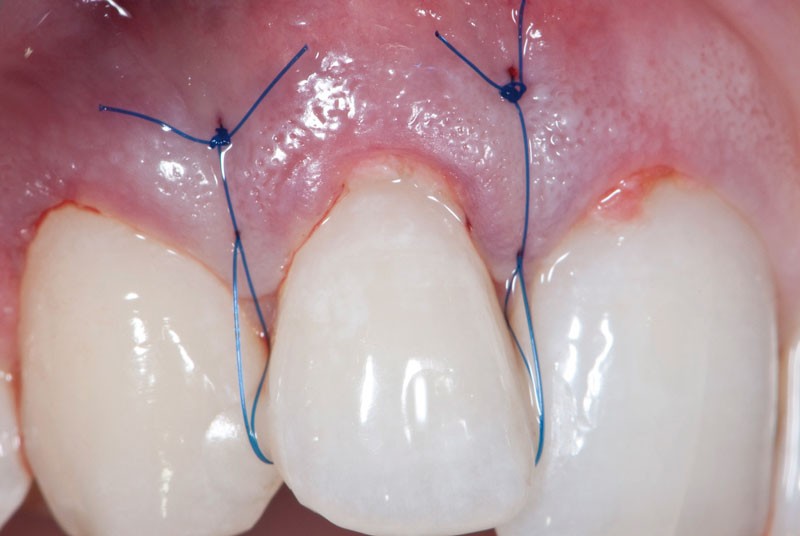

Le concept de microchirurgie a montré un intérêt croissant ces dernières années. Il permet au clinicien de réaliser des interventions chirurgicales très précises et atraumatiques avec des instruments plus petits et des sutures plus fines. Mais, y a-t-il des bénéfices cliniques mesurables ? Les principes de microchirurgie procurent-ils de réels avantages s’ils sont comparés aux concepts conventionnels de chirurgie parodontale ? La conférence du Docteur Zuhr répondra à ces questions et présentera une synthèse des innovations et des évidences scientifiques dans ce domaine.

Jeudi 7 mai : « Appliquer les principes de microchirurgie en parodontologie et en implantologie », conférence du Dr Otto Zuhr

Jeudi 7 mai : « Appliquer les principes de microchirurgie en parodontologie et en implantologie », conférence du Dr Otto Zuhr